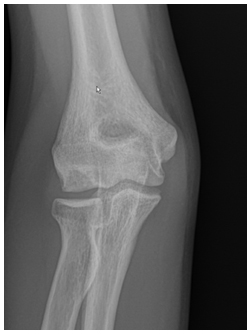

- Radiographs are used to detect the size, location and severity as well as skeletal age of the patient.

- Contralateral X-rays can help determine patients age as the affected side will have premature closure of the capitellum and radial head physes with delayed closure of the medial epicondyle and olecranon physes secondary to valgus stress overload

X-rays demonstrate a large lateral lesion within the capitellum consistent with an OCD lesion. The articular surface appears irregular

- Various classification schemes help determine severity. This includes:

- Grade I: Localized Flattening of articular cartilage

- Grade II: Nondisplaced fragmentation of the cartilage

- Grade III: Displaced or detached fragments/sclerosis or loose bodies

***Location of lesion on capitellum is important because lateral lesions tend to have inferior outcomes than central lesions

*** Throwing athletes tend to have more anterior lesions compared to gymnasts

- “Stable” lesions have been defined as those with open capitellar physis, localized flattening and radiolucency of subchondral bone with near normal elbow range of motion. Grade I is considered stable and Grade III is unstable. Grade II can be stable or unstable